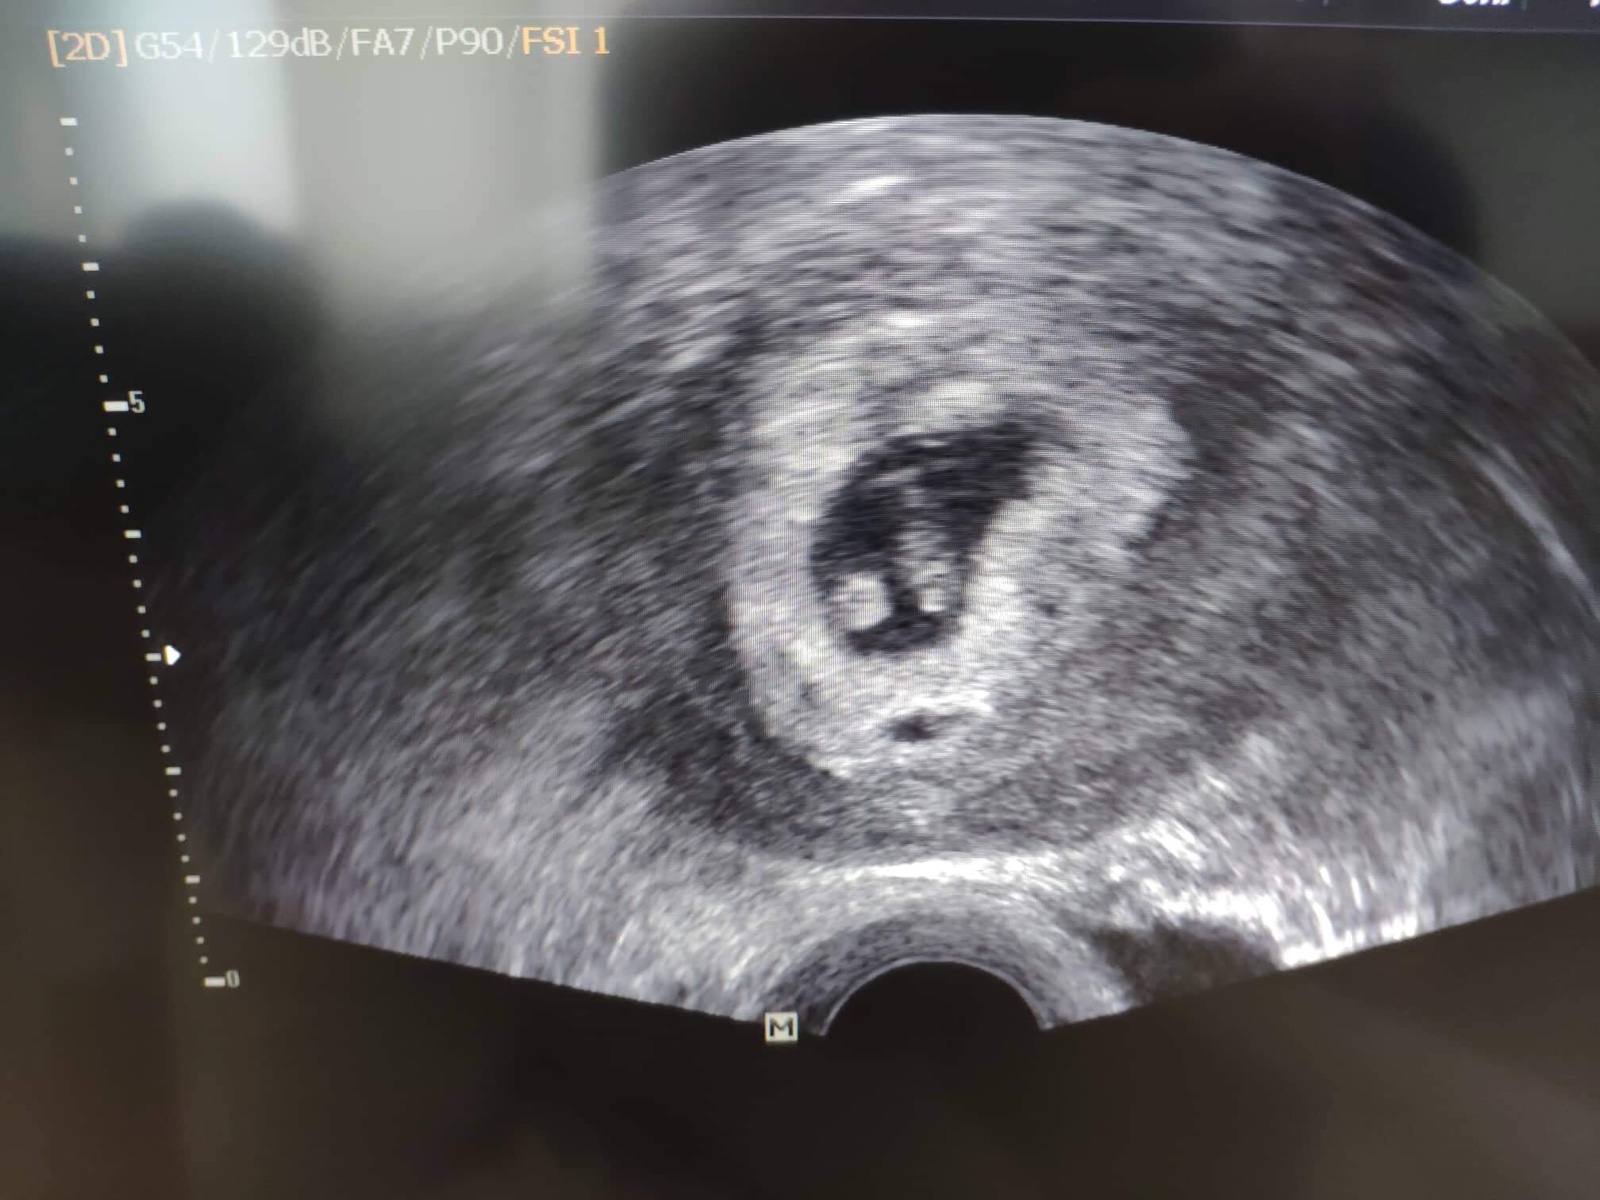

Teď jsem po KET, zbylo nám jedno vyšetřené embryo, tak jsme to zkusili. Včera jsem byla osmý den, test moc pozitivně nevypadal, zkusím znova b sobotu, no a v úterý na krvi budeme mít jistotu....

Ahoj holky, tak dalsi kontrola zamnou a vse v poradku 😍